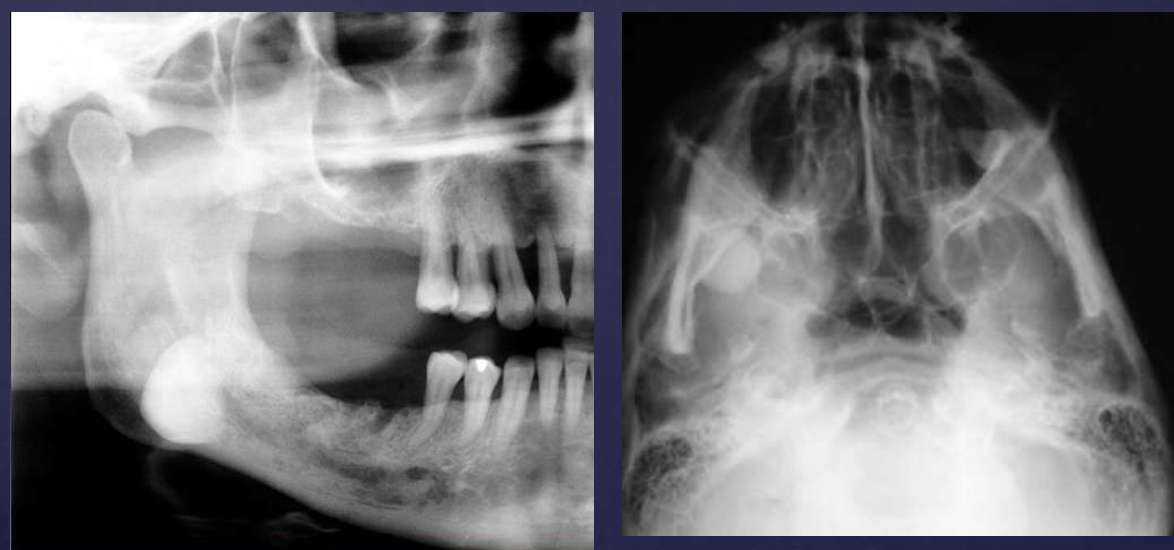

cementoblastoma

how do cementoblastomas present radiographically?

Multiple punctate radiopacities within a welldefined radiolucency

Homogeneous radiopaque mass

Mass attached to 1st mandibular molar roots

Obscured root outline, resorption

Radiolucent halo - continuity with PDL

Sclerotic border

cementoblastomas are in continuity with …?

root of a tooth (this feature differentiates it from osteoblastomas)

cementoblastomas

external root resorption 30

displacement of IAN canal inferiorly

thinning/expansion of inferior border of mandible